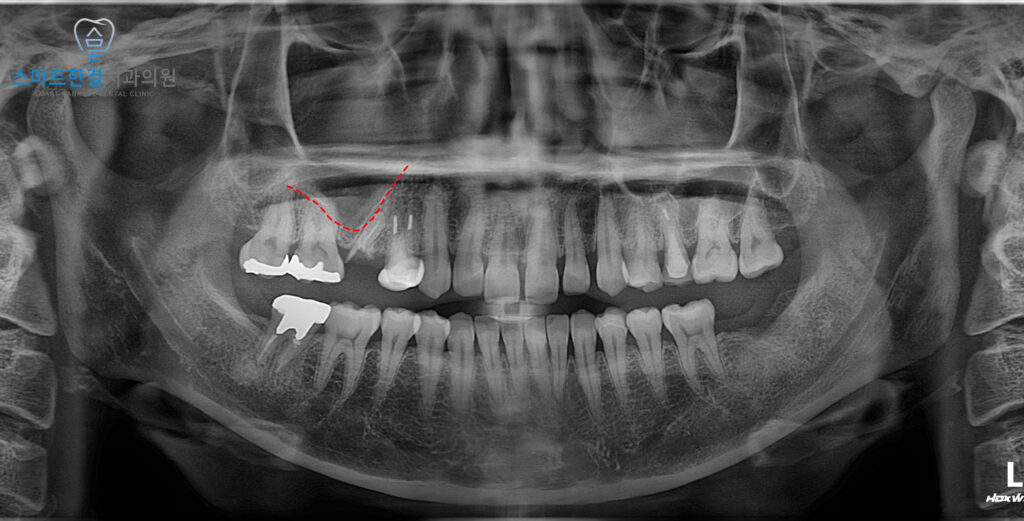

해당 부위는 상악동이 많이 내려와 있는 상태였고,

상악동의 영향으로 기존 치아의

뿌리 또한 옆으로 휘어 있는

형태를 보이고 있었어요.

이로 인해 발치 후 임플란트를 바로 식립하기에는

잇몸뼈의 높이가 충분하지 않아

안정적인 고정을 기대하기

어려운 상황이었는데요.

그래서 화서동치과 스마트한결에서는

치아를 발치 후 경사면을

이용한 상악동거상술을 통해

부족한 잇몸뼈 공간을 확보한 뒤,

임플란트를 식립하는 치료 계획을 수립했답니다!